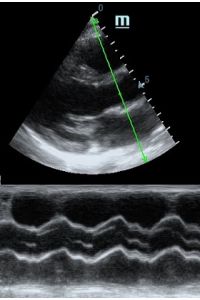

Но как же провести стандартные измерения в М-режиме, если мы его не использовали? На помощь приходит функция Free Xros M – анатомический М-режим. Имея записанную в память прибора видео петлю, мы можем провести линию М-режима в любом месте, при этом корректируя изначально не оптимальный угол.

Возможности применения функции многогранны: от измерения толщины стенок левого желудочка, движения створок митрального клапана и кооптации нижней полой вены до оценки сократимости миокарда как глобально, так и по сегментам.

Показатели УЗ сканирования в М-режиме

Какие показатели можно использовать при анатомическом М-режиме помимо привычных срезов через конец створок митрального клапана или синуса Вальсальве?